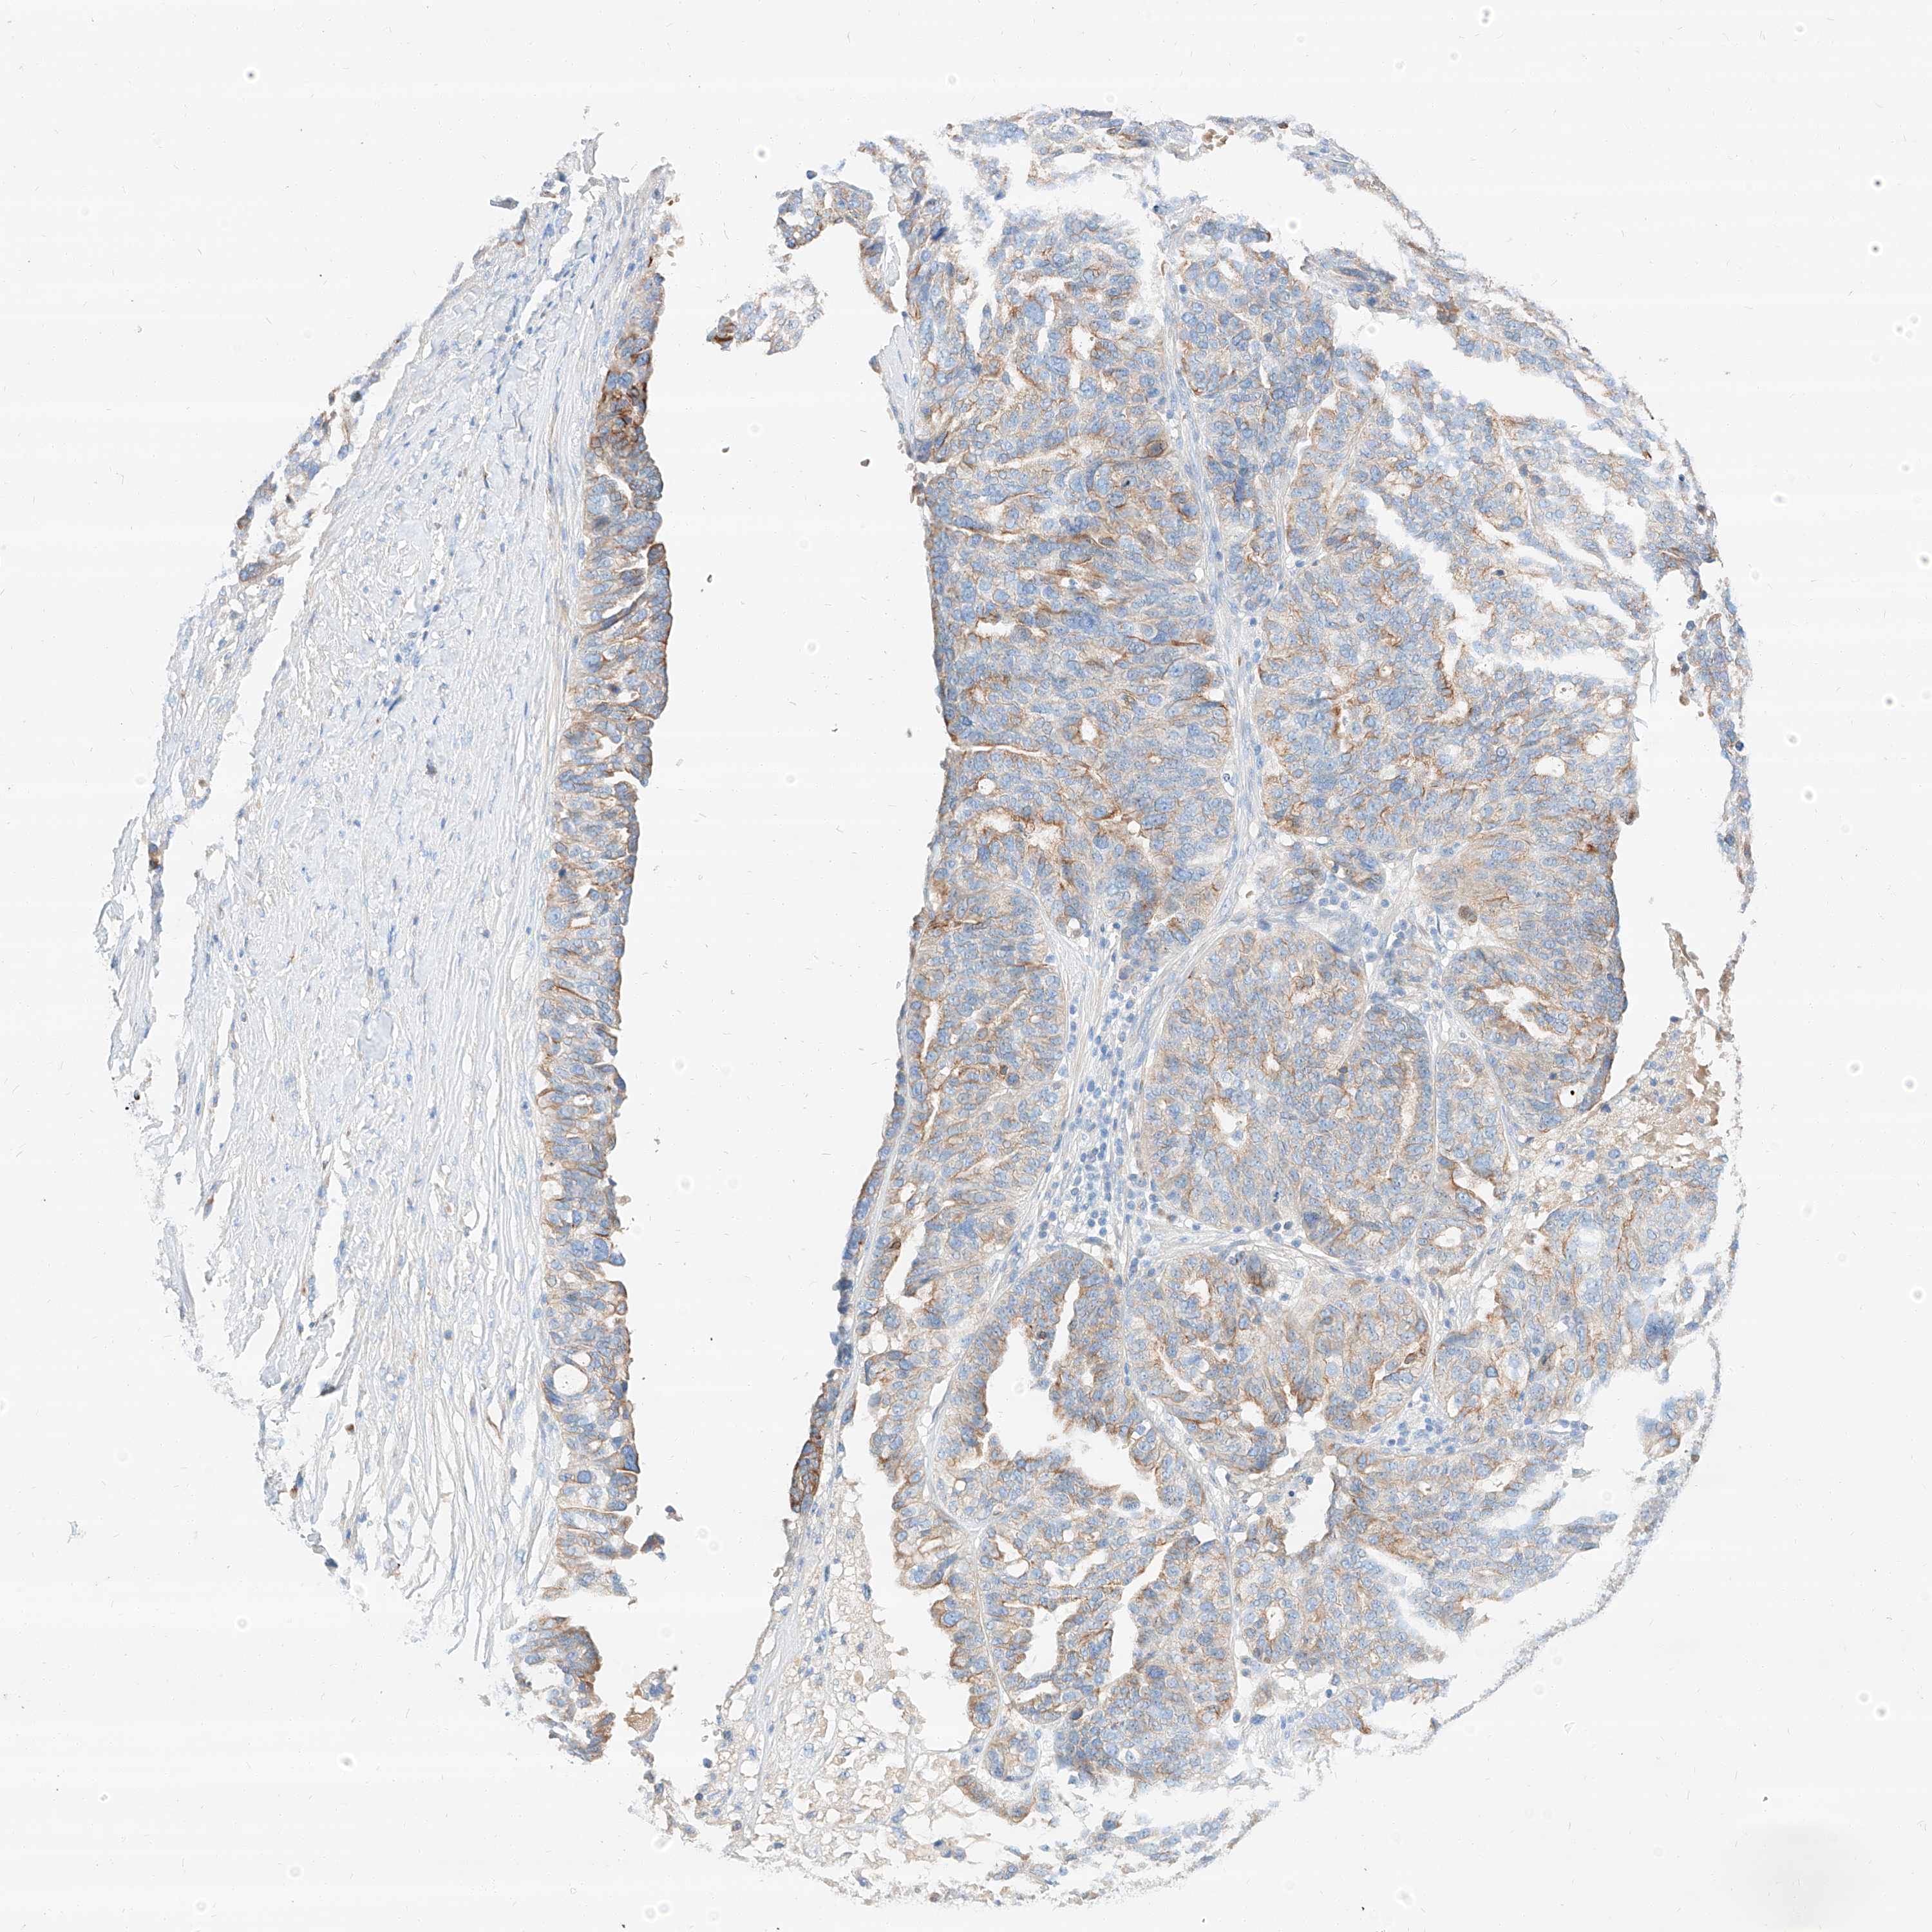

OVARIAN CANCER - Protein expressioni

A mouse-over function shows sample information and annotation data. Click on an image to view it in a full screen mode. Samples can be filtered based on level of antibody staining by selecting one or several of the following categories: high, medium, low and not detected. The assay and annotation is described here.

Note that samples used for immunohistochemistry by the Human Protein Atlas do not correspond to samples in the TCGA dataset.

Antibody stainingi

Antibody staining in the annotated cell types in the current human tissue is reported as not detected, low, medium, or high, based on conventional immunohistochemistry profiling in selected tissues. This score is based on the combination of the staining intensity and fraction of stained cells.

Each image is clickable and will lead to virtual microscopy that enables deeper exploration of all samples and also displays staining intensity scores, fraction scores and subcellular localization as well as patient and tissue information for each sample.

Antibody HPA029712

Antibody HPA029713

Cystadenocarcinoma, serous, NOS

Carcinoma, endometroid

Cystadenocarcinoma, mucinous, NOS

Carcinoma, NOS